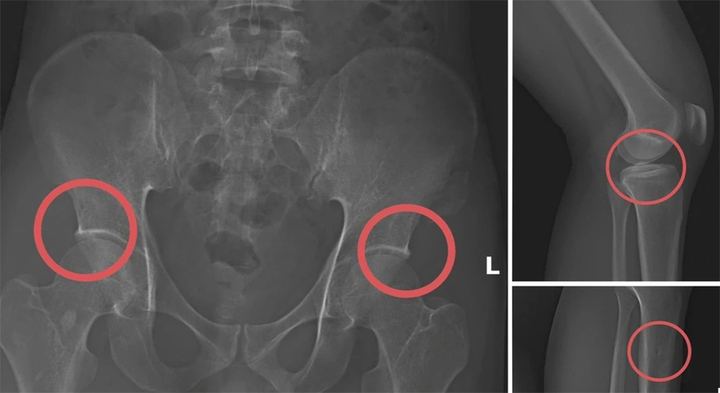

Tự đục vỡ xương để trục lợi bảo hiểm: Quá sợ kẻ vì tiền mà độc ác với chính mình

Chịu đục xương để trục lợi bảo hiểm, với chính cơ thể mình mà còn đối xử tàn nhẫn như vậy thì họ sẽ đối xử ra sao với người khác khi có cơ hội kiếm lợi?